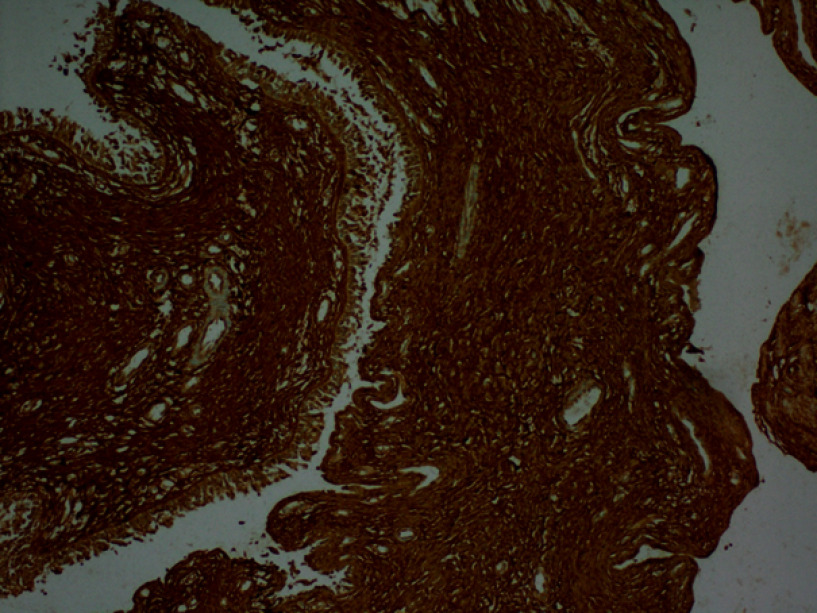

Aim: This study aimed to compare the immunohistochemical staining patterns of periostin, fibronectin, and tenascin-C in sinonasal lesions to elucidate their roles in pathogenesis and enhance differential diagnosis.

Methods: In this retrospective study, pathological specimens from 70 patients who underwent surgery for sinonasal polyps were analyzed. Immunohistochemical expression of periostin, fibronectin, and tenascin-C was assessed separately in epithelial and stromal compartments using a semi-quantitative scoring system. Associations between staining patterns and lesion types were evaluated using multinomial logistic regression.

Results: The cohort had a male-to-female ratio of 5:2 with a mean age of approximately 40 years. Nasal polyps demonstrated significantly higher stromal periostin staining compared to both antrochoanal polyps and inverted papillomas. Conversely, antrochoanal polyps exhibited significantly elevated epithelial periostin expression relative to inverted papillomas. Fibronectin expression was markedly increased in nasal polyps, especially in the stroma, supporting its role in inflammatory tissue remodeling. Tenascin-C expression did not differ significantly among the lesion types.

Abstract Image